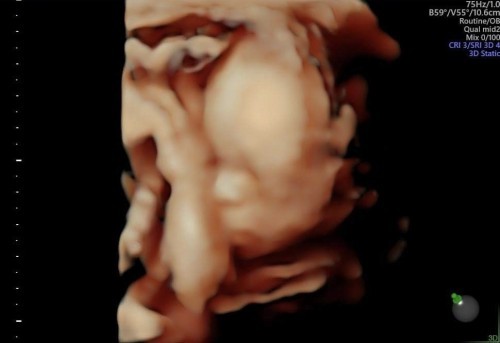

22 week🥰 ครึ่งทางแล้ว

ปิดหน้าเก่งมากหมอต้องซาวด์กันเป็นชั่วโมงเลยค่ะ😅